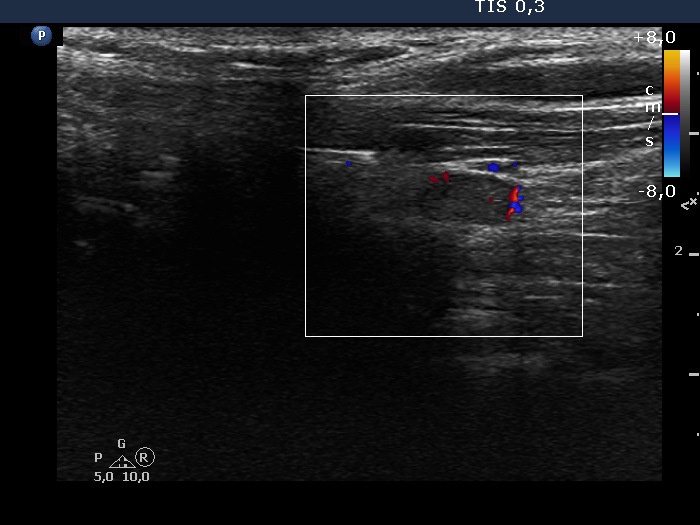

Ultrasonography revealed that the discrete hypoechoic lesion in the left lobe had increased in size, the dimensions were 4x4x5 mm, width, depth and length, respectively. There was a lymph node lateral to the left lobe. The node presented a heterogeneous pattern and lacked a regular hilum.Suggestion: repeat ultrasound in 3 to 6 months.

However, the lymph node is suspicious, especially due to its heterogeneity.